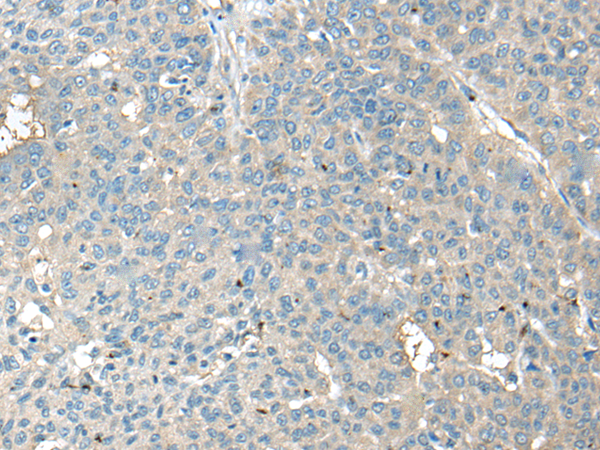

分类: 科研抗体货号: P09447别名: JM11应用: IHC反应种属: Human, Mouse